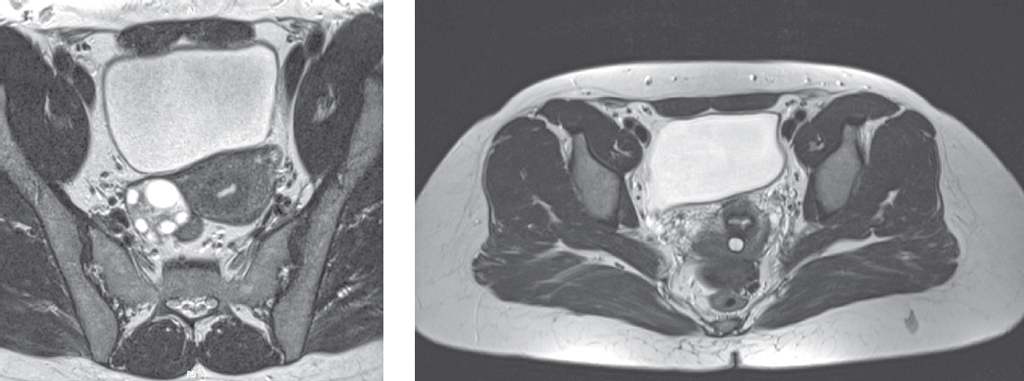

In our clinical case, according to the results of MRI of pelvic organs, the 38-year old patient had a cyst in posterior cul-de-sac with hemorrhagic or high-protein contents, and also the left ovary was not visible. During the laparoscopy an autoamputation of the left uterine adnexa due to torsion was found, as well as presence of necrotizing lesion in posterior cul-de-sac. Thus, laparoscopy is the only reliable method for diagnosing and treating adnexal torsion.